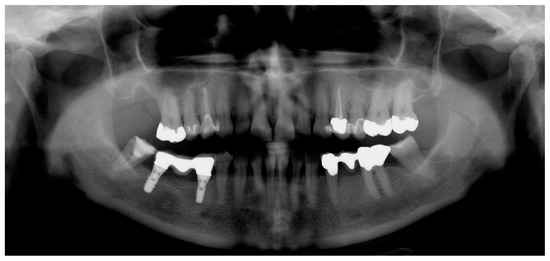

2.2. Radiographic Methods

2.3. Analysis of Radiographic Images